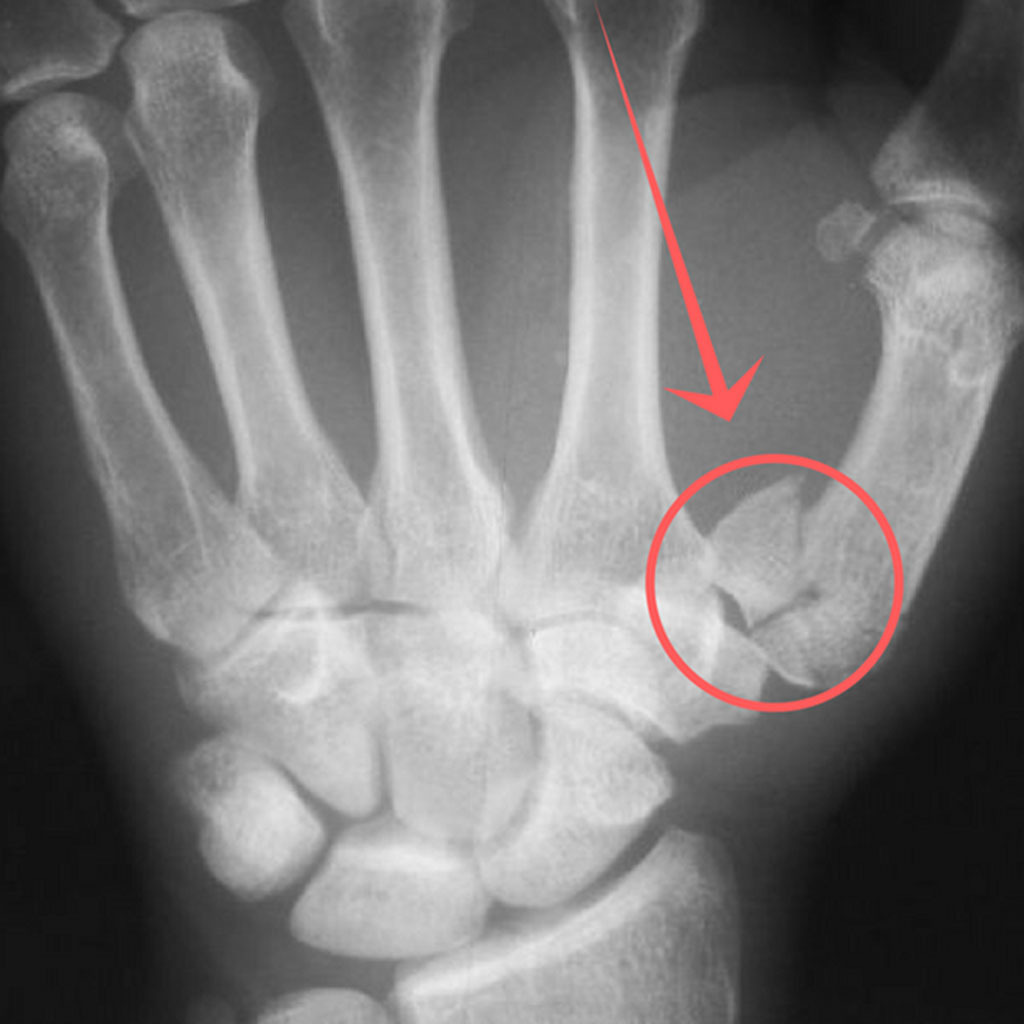

손가락 골절은 기저부(base) 골절, 중간부(shaft) 골절, 관절면(intra-articular) 골절 등으로 나뉘며, 특히 관절면을 침범한 골절은 기능적 후유증이 남을 위험이 높습니다. 따라서 엑스레이 검사로 정확한 위치와 손상 정도를 파악하고, 필요 시 CT나 초음파로 인대 손상 여부를 함께 확인해야 합니다.

손가락에 금이 갔을 때 무조건 깁스를 해야 하는 것은 아닙니다. 뼈가 어긋나지 않은 단순 골절이라면 스플린트나 버디 테이핑만으로도 충분히 치료가 가능합니다. 깁스는 뼈가 크게 전위되었거나, 여러 조각으로 부서졌을 때, 혹은 골절선이 관절면을 침범해 안정적인 고정이 필요한 경우에만 시행합니다.

발가락 골절의 경우에는 뼈가 어긋나 유합되면 걸음걸이가 비틀리거나 신발 착용 시 통증이 지속될 수 있으므로, 4주차에 X-ray 재검을 반드시 받아야 합니다. 또한 당뇨병이나 골다공증 환자는 회복이 느리기 때문에, 일반인보다 1~2주 더 긴 고정 및 재활 기간이 필요합니다.